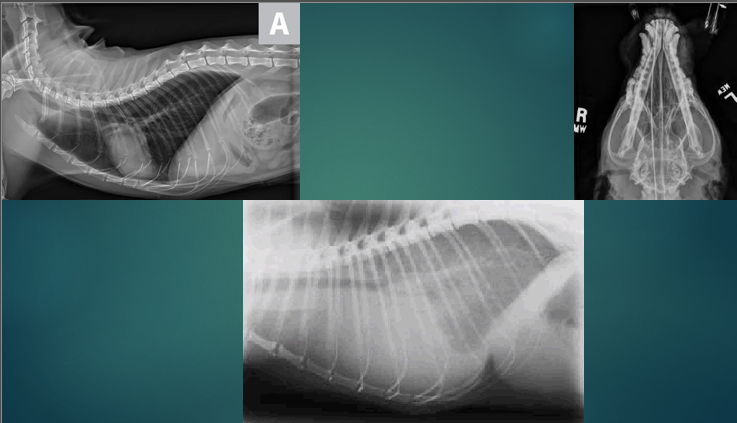

Diagnosis - Radiography

Image of head and nasal cavities and chest

Will show if there is any inflammation, obstruction, foreign bodies or masses

Can see if there is any Fluid in the lungs - air is black on an x-ray so if there is any fluid this will be seen clearly